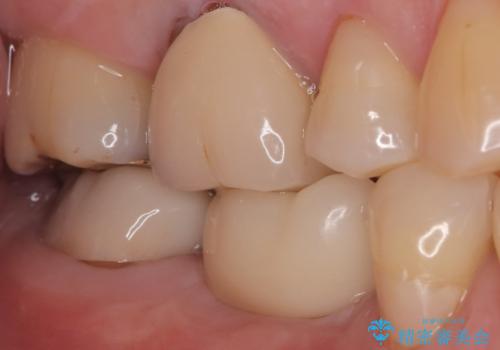

- 奥歯の欠損をインプラントで治療したいと来院された患者様です。

骨の状態が安定するまで待機したのち、インプラントを埋入しています。

スクリューリテインにて上部構造を連結しています。